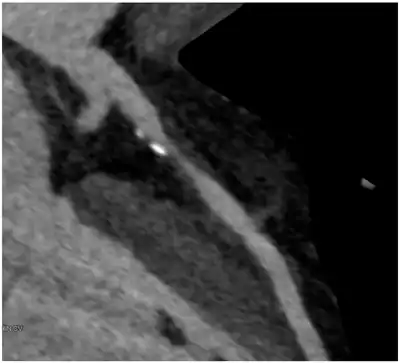

| Image of contrast enhanced dual-source coronary CT-angiograph | |